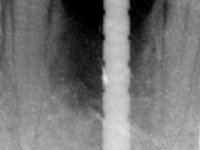

• After two months, a CBCT scan to plan one dental implant and the type of bone regeneration to be performed. Due to the lack of mesiodistal space, the option for two dental implants was dropped.

After the CBCT evaluation, our option was to place the dental implant in the central position of the edentulous area for 4 mains reasons:

• Preservation of the bone in the mesial surfaces of the adjacent teeth.

• The thickness (buccal-lingual) was higher in the area.

• Biomechanical, the position was more favourable.

• The esthetic rehabilitation with gum-shade ceramics was easier with the implant placed in this position.